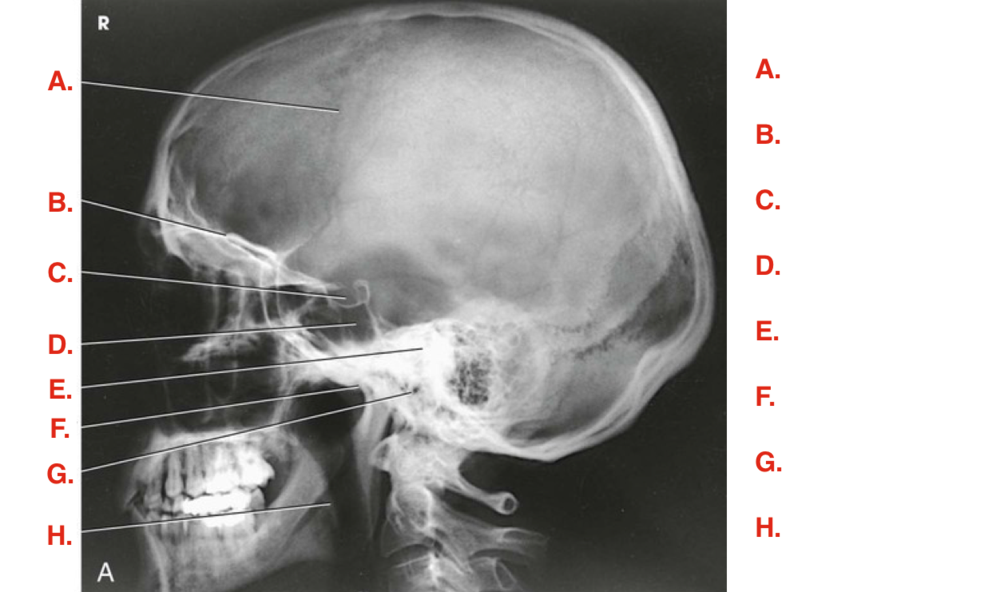

Question 3

Question

Label the image

Image:

63ad82cd-14c0-428c-8e21-c82af949e359 (image/png)

Answer

parietal bone

frontal bone

dorsum sella

superior orbital margin

petrous ridge

crista galli

ethmoid sinus